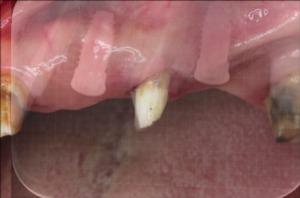

こちらの患者さまは、左上の歯にうずくような痛みがあるとのことで、貴和会新大阪歯科診療所にご来院されました。

詳しく診査・診断した結果、他院で作製された義歯の金具を支えていた歯が破折していたため、義歯装着時に掛かる負荷によって痛みが生じていたことがわかりました。

治療前